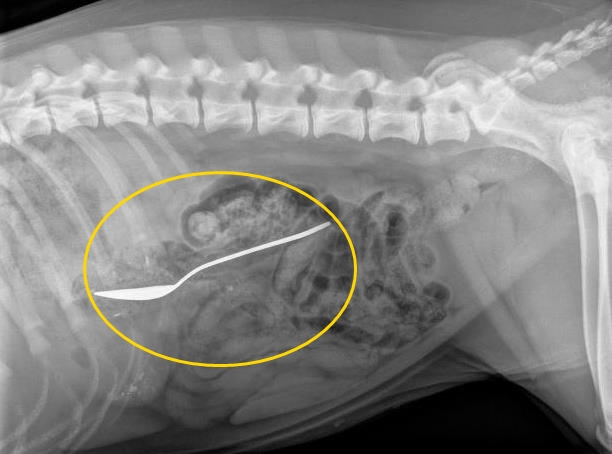

허먼의 짐작은 적중했다. X-레이 촬영결과 집시의 위에서 커다란 티스푼이 발견 된 것이다. 당시 진찰을 맡은 수의사 데이비드 로빈슨은 “조금만 늦게 왔어도 목숨이 위험했을 것”이라며 상황이 급박했음을 강조했다.

현재 집시는 응급수술로 숟가락을 제거한 상태며 매우 건강한 것으로 알려졌다.

사진=뉴욕데일리뉴스 캡처